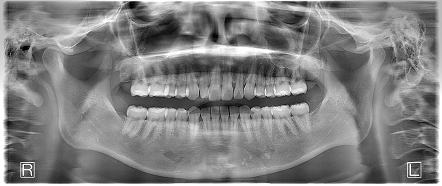

反対咬合を伴う下顎前歯叢生 【20代・女性】

- 左上と下の左右に親知らずがあり、インビザラインの治療前に親知らずの抜歯を行ったケースです。

- 上下の歯列のガタツキは矯正治療前よりも改善され、上下の咬合関係も良好になりました。